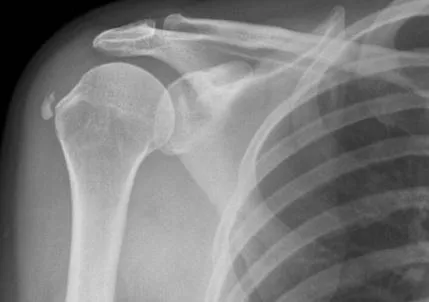

- Rotator cuff tendinopathy

- Calcific shoulder conditions

Conditions like plantar fasciitis, tennis elbow, and rotator cuff issues often fall into this category. In these cases, the body struggles to restart the healing process on its own.